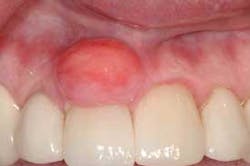

Notes and findings: The patient is a 51-year-old white female maintenance patient who has not had a dental appointment in over two years. She scheduled an appointment because a large growth is noticeable in the anterior region of her mouth, and this lesion has her concerned. The patient reports that the growth has been there for over one year and has grown considerably during that time. As the oral tissues are assessed, it is noted that the large lesion in the anterior is firm, smooth, and sessile (broad-based). The patient reports no pain, but does report that the growth can become somewhat ulcerated if she brushes too hard or traumatizes the area (see Figure 1).

Perioral and intraoral characteristics: The lesions are normally found on the attached gingiva. The abundance of tissue is usually the same color as the surrounding tissue, with a smooth surface. Sometimes the surface may be more textured, depending upon the existing oral forces and location in the patient’s mouth. Additionally, the surface epithelium may be more of a dark color depending upon the amount of trauma and inflammation that is produced with the lesion.